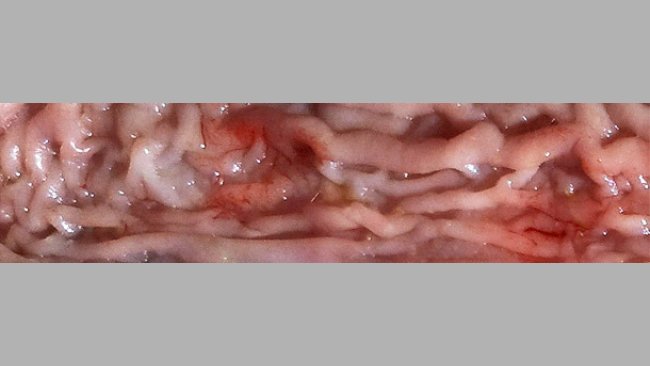

L'ileite si presenta in differenti forme, assieme nella stessa popolazione e risulta frequente che coincidano la forma subclinca con forme più gravi e acute.